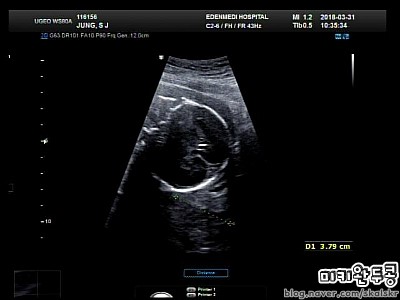

21주 5일_ 2018.3.31 중기 정밀 초음파 본날

21주 5일_ 2018.3.31 중기 정밀 초음파 본날 안녕하세요. 미키완두콩이에요. 중기 정밀 초음파를 본날도 벌...